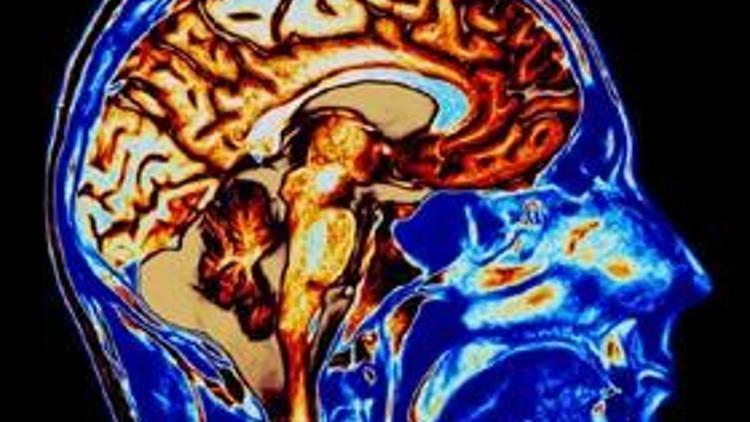

Beynin sırrı çözüldü

Bilim adamları, beyinde insanları serüvene iten bir merkez buldu.

İngiliz araştırmacılar, beyindeki kan akışını ölçerken, deneklerin olağan dışı nesneleri seçtiği zaman beyinde "ventral striatum" olarak bilinen bölgenin daha çok faaliyete geçtiğini buldu.

Araştırma ekibinin başı doktor Bianca Wittmann, "yeni ve bilinmedik tecrübeler arayışının, insanlar ve hayvanların temel davranış eğilimlerinden biri olduğunu" belirtti. Wittmann, avantajları uzun dönemde görülecek olsa da yeni seçenekleri denemenin akla uygun geldiğini de kaydetti.

İngiliz araştırmacılar, beyindeki kan akışını ölçerken, deneklerin olağan dışı nesneleri seçtiği zaman beyinde "ventral striatum" olarak bilinen bölgenin daha çok faaliyete geçtiğini buldu.

Araştırma ekibinin başı doktor Bianca Wittmann, "yeni ve bilinmedik tecrübeler arayışının, insanlar ve hayvanların temel davranış eğilimlerinden biri olduğunu" belirtti. Wittmann, avantajları uzun dönemde görülecek olsa da yeni seçenekleri denemenin akla uygun geldiğini de kaydetti.